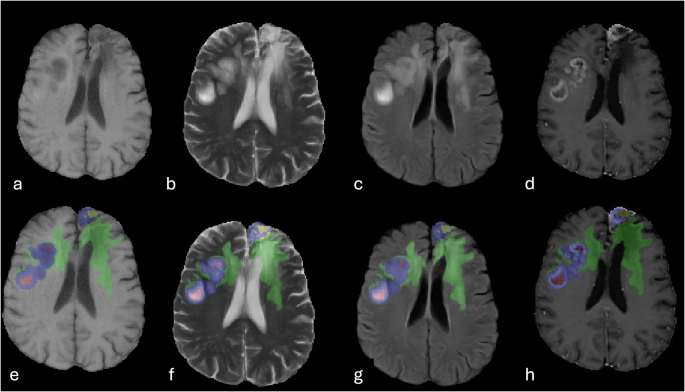

The pipeline resulted in tumor segmentations with four distinct labels that correspond to different components of each tumor (Fig. 3):

-

Label 1: Non-enhancing Tumor Core (NETC). This label identifies non-enhancing components within the tumor, such as cystic, necrotic, or hemorrhagic portions.

Label 2: Surrounding Non-enhancing FLAIR Hyperintensity (SNFH). This label represents both non-enhancing infiltrative tumor components and peritumoral vasogenic edema.

Label 3: Enhancing Tissue (ET). This label highlights the viable nodular enhancing components of the tumor.

Label 4: Resection Cavity (RC). This label covers post-surgical changes, including recent changes like blood products and air foci, as well as chronic changes with materials isointense to CSF signal.

Different segmentation sub compartments of multicentric GBM with multiple bi-cerebral heterogeneously enhancing masses. Top image panel (a–d) shows the pre-segmented, co-registered and skull stripped T1 weighted image (a), T2 weighted image (b), FLAIR image (c), and T1 following IV gadolinium-based contrast administration (d). Bottom image panel (e–h) demonstrates the overlay of the different segmentation labels in respect to the corresponding tumor sub-compartment i.e. enhancing tumor (blue), non-enhancing tumor core (red), surrounding non-enhancing T2/FLAIR hyperintensity (green), and the resection cavity (yellow).